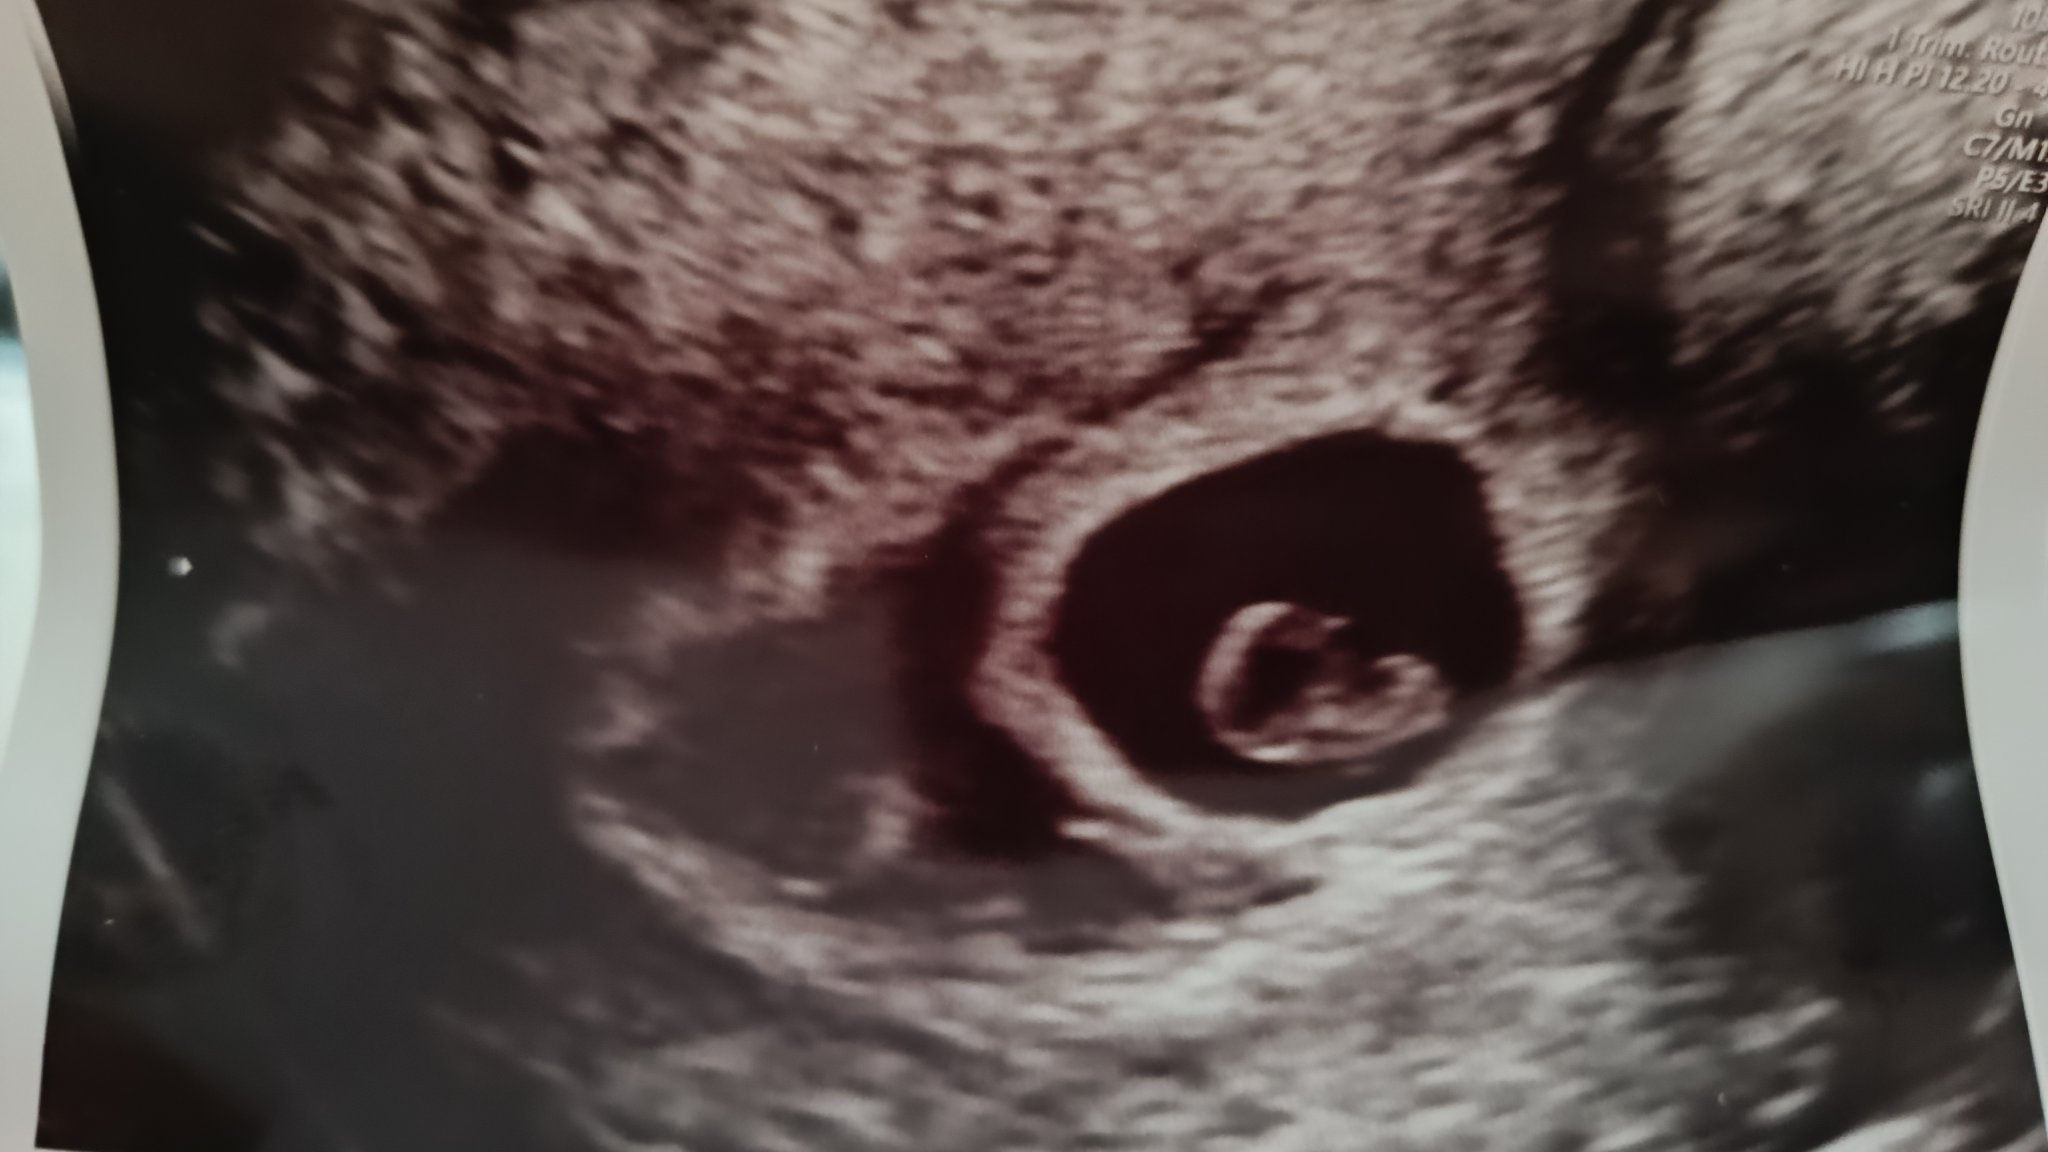

Здравейте, преди седмица ви споделих, че получих кафяво зацапване, вчера бях на преглед отново и се видя отлепване на плодния сак. В 6+4г.с съм докторът ми написа болничен и каза да почивам.

Имам нужда от кураж! По снимката ми се струва доста голямо отлепване, въпреки че доктора нищо не каза за размерите ...

Моля споделете имали ли сте отлепване в ранна бременност? Как се развиха нещата?